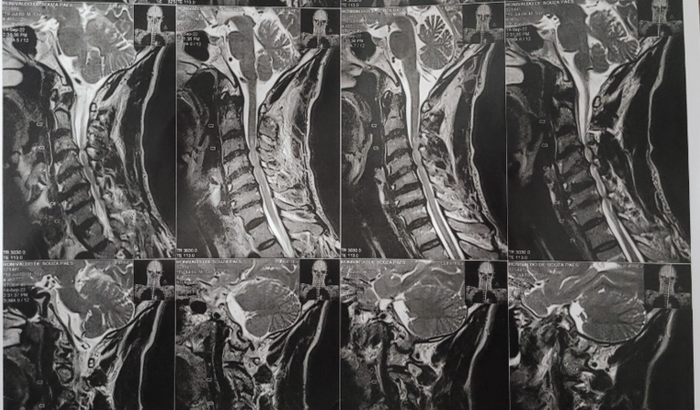

Hoje em decorrência de todos esses anos pegando no pesado, desenvolvi uma condição severa na coluna cervical chamada Mielopatia Espondilótica, que se trata de uma compressão da medula espinhal devido ao estreitamento degenerativo do canal vertebral. A coluna fica tão estreita que afeta a medula que é por onde passa os sinais do cabeça para o corpo. Esta doença me impede de trabalhar e até fazer coisas simples como ficar sentado em frente a TV.

A única forma de reverter o meu quadro é através de uma descompressão cirúrgica. Ou seja caso eu não realize a cirurgia, minha condição pode evoluir para cadeira de rodas.